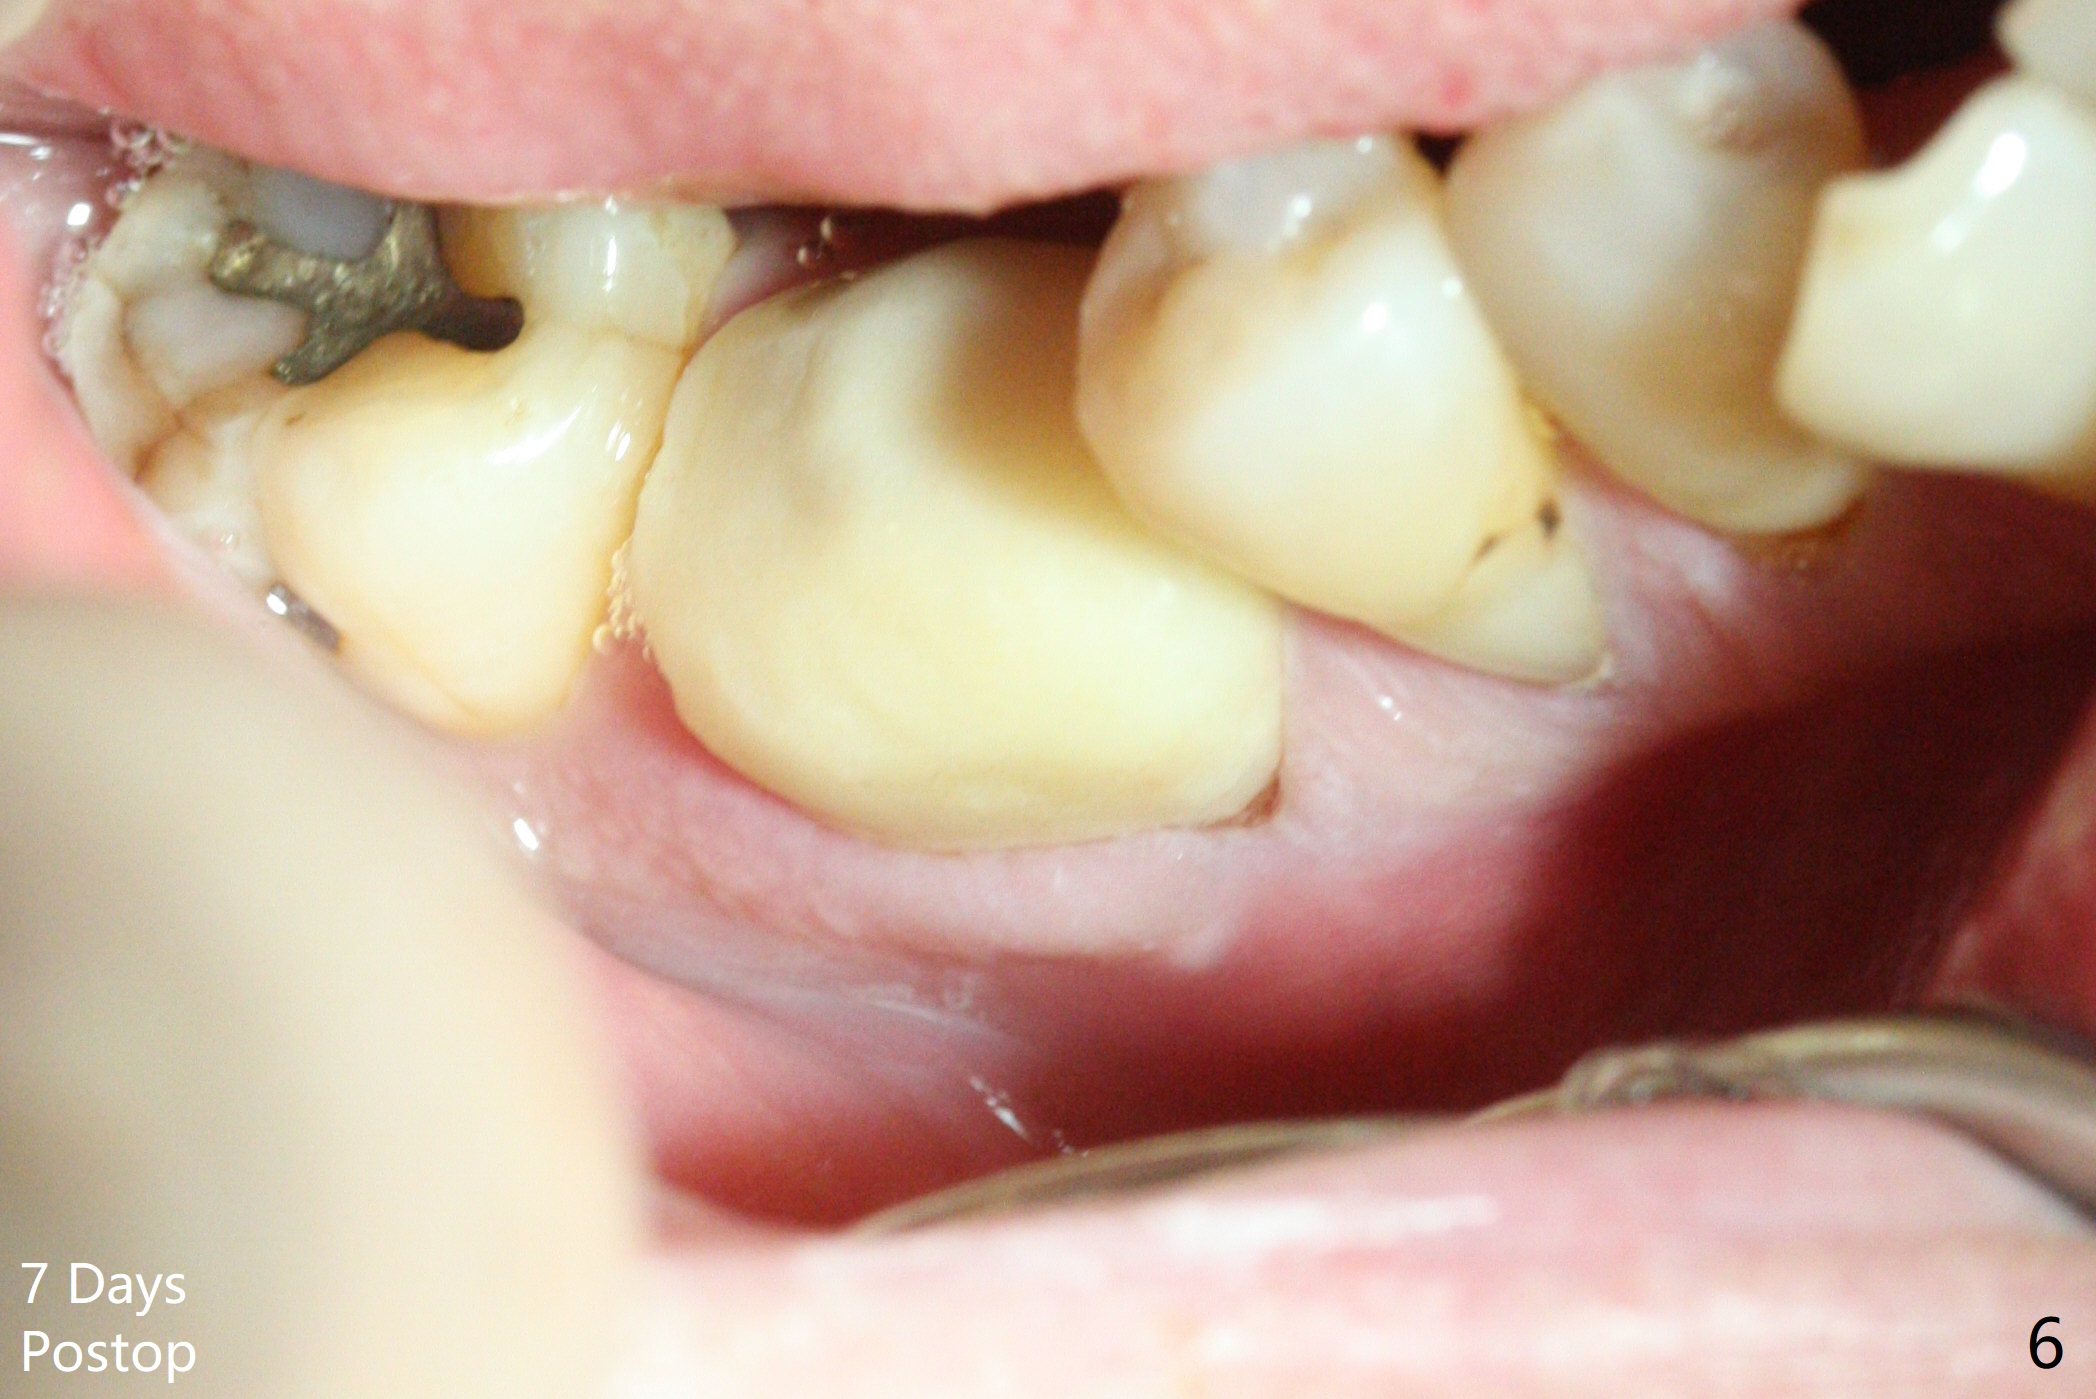

After extraction of the tooth #30, the mesiobuccal plate is found to be lost, corresponding to the fistula (Fig.1 <). Osteotomy is initiated in the flattened septum (lingual) for 13 mm (Fig.2). The patient feels pain when larger drills are being used. Marcaine has to be injected in an infiltration manner for pain control. When a 4.5x10 mm dummy implant is inserted with 55 Ncm, the end of the osteotomy (Fig.3 white line) is close to the Inferior Alveolar Canal (red dashed line). When a definitive implant (Fig.4: 4.5x11.5 mm) is placed with primary stability, there is an apical space (Fig.5 white double arrows). There is moderate postop pain. A shorter implant (10 mm) should be tried when the bone is dense. It will be associated with less pain. The fistula disappears 7 days postop (Fig.6). Although the patient appreciates that the pain is gone, there is atrophy mesiobuccally 2 months postop (Fig.7 *). The implant seems to be have been placed too buccally (Fig.8). With loss of the buccal plate, the implant should be placed away from it to prevent periimplantitis. The abutment is changed from 6.5x4(4) to 6.5x5.5 (3) mm with fabrication of a new provisional. The buccal margin is still supragingival 6 months postop and prep lower before impression. The mesial and distal sockets appear to have healed (Fig.9). When the crown is cemented, the mesiobuccal papilla is present (Fig.10 *), while the mesiolingual one is apparently absent (Fig.11 *). Using a temporary abutment and relining the provisional multiple times would increase the chance of rebuilding the missing papilla. The bone density around the implant increases 11 months post cementation (Fig.12). The dense (apparently cortical) bone seem to grow over the implant plateau 11 months post cementation (Fig.13 <).